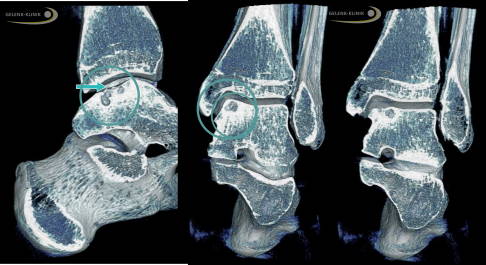

Mikrofrakturierung bei Knorpelschaden am Sprunggelenk

Eine bewährte Technik zur Regeneration des Knorpels im Sprunggelenk ist die Mikrofrakturierung. Dabei wird der unter dem Knorpeldefekt liegende Knochen mit einer Stanze bearbeitet, sodass minimale Einrisse im Knochen entstehen (Mikrofrakturen). Durch die Knochenverletzung kommt es zur Einblutung, dabei strömen Stammzellen aus dem Blut in die defekte Knorpelfläche. Diese Stammzellen differenzieren sich nach einigen Wochen zu Faserknorpel. Der Faserknorpel ist nicht ganz so robust wie der ursprüngliche hyaline Knorpel, erfüllt seinen Zweck zur Auffüllung der Knorpelfläche dennoch sehr gut.

Bild 1:

Der Knochen (grau) unter dem Knorpeldefekt (Lücke) wird mit einem kleinen Bohrer leicht angebohrt.

Bild 2:

Durch die Knochenverletzung kommt es zur Blutung (rot). Stammzellen aus dem Knochenmark strömen aus dem Knochen heraus.

Bild 3:

Die Stammzellen differenzieren sich zu Faserknorpel (hellblau), der den Defekt nach wenigen Wochen auffüllt.